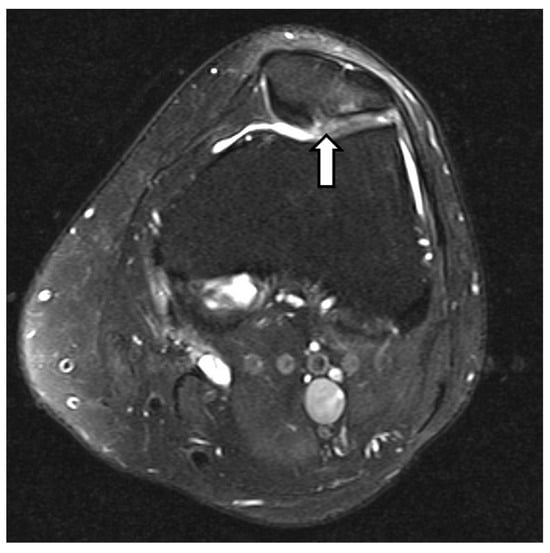

3.10. Metabolic Diseases